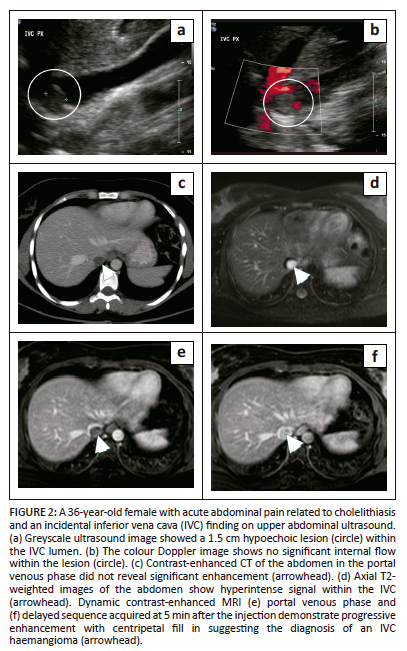

Inferior vena cava haemangioma

Haemangiomas at most locations demonstrate characteristic features allowing for a confident radiological diagnosis. However, they can occasionally occur at atypical sites and have atypical imaging features that pose a diagnostic dilemma and may necessitate surgical excision. Inferior vena cava haemangiomas are rare with a few reported cases in the literature.9,10 Multiphase CT or MRI are often needed for the diagnosis demonstrating an intraluminal mass within the IVC, indistinguishable on imaging from other IVC neoplasms (Figure 2).10